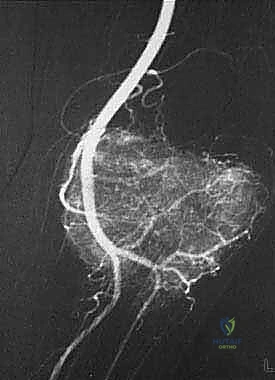

يتم فتح الجلد والأنسجة بعناية فائقة. التحدي الأكبر هنا هو فصل الورم عن الأوعية الدموية والأعصاب الرئيسية المغذية للطرف. يستخدم الدكتور هطيف تقنيات الجراحة الميكروسكوبية لضمان سلامة هذه الهياكل الحيوية، مما يحافظ على حيوية الطرف وحركته.

المرحلة الثانية: إعادة البناء العظمي (Skeletal Reconstruction)

بعد إزالة جزء من العظم (أو المفصل بأكمله)، يجب سد الفجوة. تتعدد الخيارات التقنية التي يوفرها الدكتور هطيف في صنعاء:

1. المفاصل الصناعية الكبيرة (Megaprostheses): مفاصل معدنية متطورة (من التيتانيوم) تُصمم خصيصاً لتعويض العظم المفقود، وتسمح للمريض بالحركة المبكرة.

2. الطعوم العظمية (Bone Grafts): استخدام عظم من بنك العظام (Allograft) أو من المريض نفسه (Autograft)، مثل نقل عظمة الشظية مع أوعيتها الدموية لضمان التئامها السريع.

- الجراحة الميكروسكوبية (Microsurgery): لخياطة الأوعية الدموية والأعصاب الدقيقة التي لا تُرى بالعين المجردة، مما يضمن تدفق الدم للطرف بعد الاستئصال الواسع.